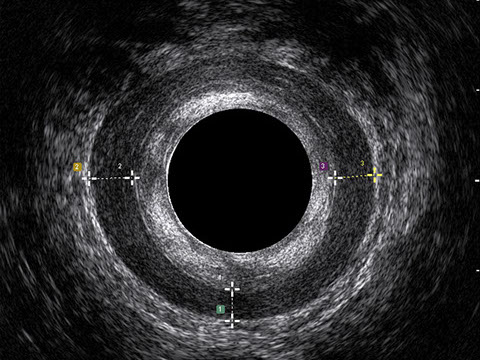

L’ecografia transanale è un esame diagnostico per immagini che consiste nell’introduzione di un trasduttore ad ultrasuoni. Le immagini qualitativamente migliori del canale anale sono ottenute usando un trasduttore rotante, montato in un manipolo rigido, che fornisce un’immagine a 360°. Con le apparecchiature più moderne è anche possibile ottenere immagini tridimensionali.

L’ecografia transanale permette di distinguere la sottomucosa che riveste il canale anale, lo sfintere anale interno, e lo sfintere anale esterno.

Proctal dispone di apparecchiatura per ecografia endoanale 3D con sonda rotante.